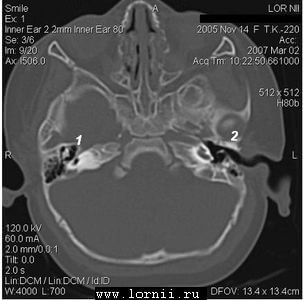

КТ височных костей выявила наличие двухсторонней аномалии развития улитки в виде неполного разделения I типа (табл. 4). При этом данное утверждение верно как для левого, так и для правого уха, несмотря на различную, на первый взгляд, картину (рис.1).